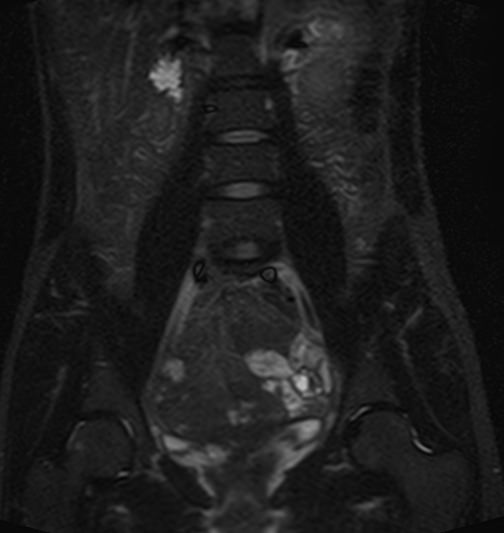

Скрининговое обследование всего тела с помощью метода магнитно-резонансной томографии включает в себя сканирование головы, шеи и туловища с органами брюшной полости, забрюшинного пространства и малого таза.

• органов малого таза (мочевой пузырь, прямая кишка, матка и яичники у женщин, предстательная железа и семенные пузырьки у мужчин);

Метод позволяет выявить бессимптомные потенциально опасные для жизни состояния, например опухолевые образования, которые долгое время себя никак не проявляют и могут обнаруживаться уже в запущенных случаях. К примеру, опухоли яичников, почек, печени, когда раннее выявление процесса значительно повышает шансы пациента на успешное лечение и выздоровление. Также МР-скрининг может проводится в профилактических целях пациентам, у которых есть близкие родственники с онкопатологией, чтобы вовремя выявить начало болезни.

МР-скрининг проводится без контрастного усиления. Если во время процедуры врач-рентгенолог выявит зоны патологически измененного МР-сигнала, то вторым этапом станет повторное проведение диагностики, но уже прицельно той области, где были выявлены изменения. Повторное исследование оплачивается отдельно и проводится в другой день, как правило, с применением контрастирования.

МРТ с контрастом необходима для получения более точных сведений о структуре, размере, распространенности патологического процесса и некоторых других его параметрах (например, является ли он опухолевым)